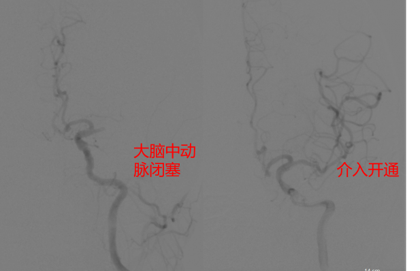

1.急性缺血性卒中桥接治疗

对于急性大血管闭塞性脑梗死,给予静脉溶栓+动脉取栓治疗,血管开通成功率在95%以上,术后90天良好预后率达70%,达到省内领先水平。

急诊介入取栓术